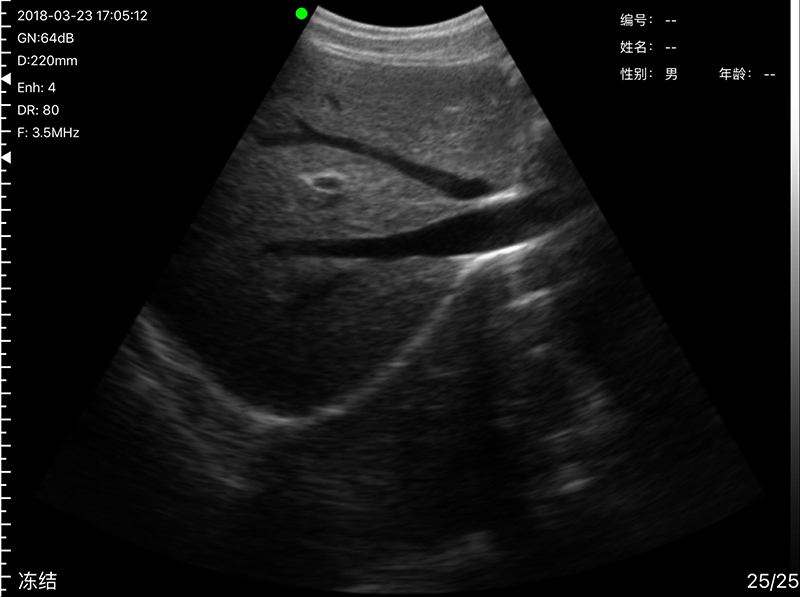

• Probe Head: R60 Convex+R13 Transvaginal

Convex head 3.2MHz/5MHz, 90/160/220/305mm, R60